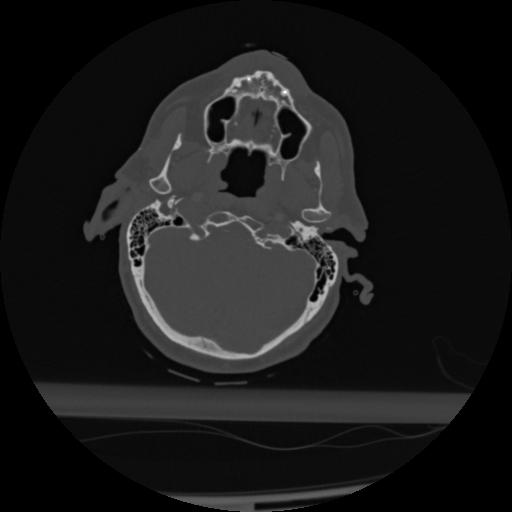

22 ANGIO,CE,Vol,0.5,ANGIO,,